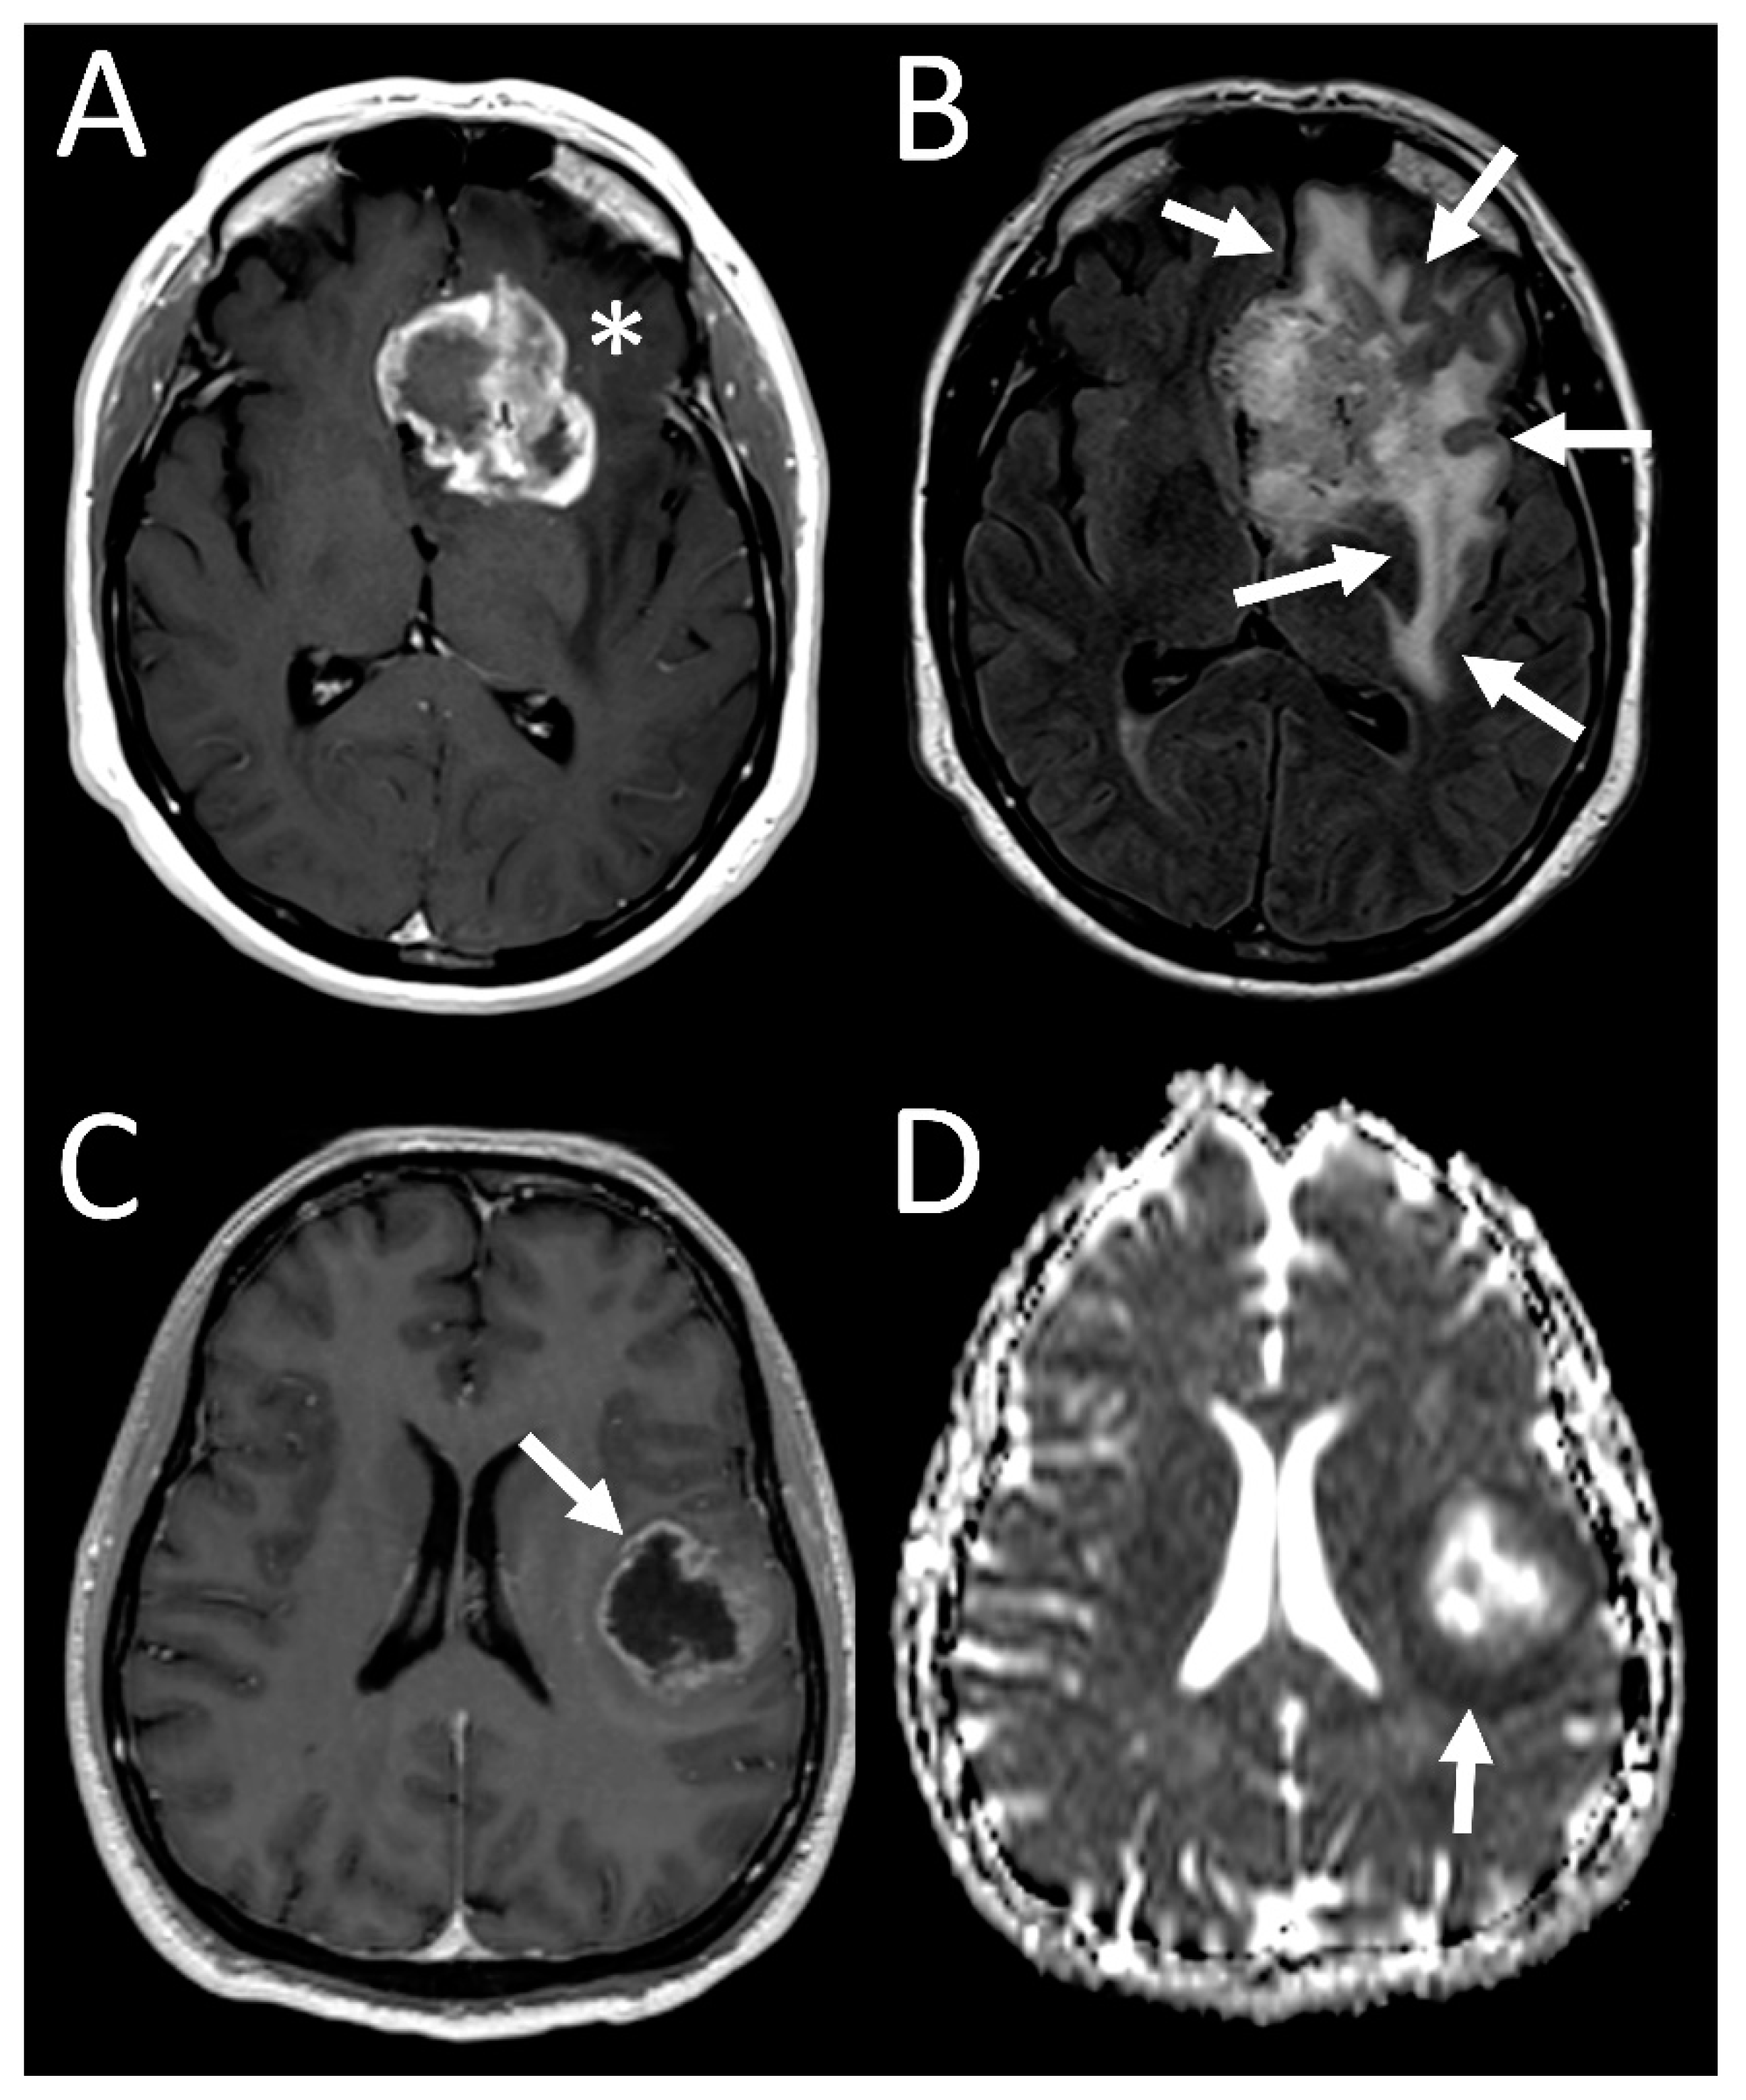

3.4. Tumor Characteristics